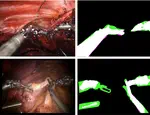

We have recently published the paper “Garcia-Peraza-Herrera, L. C., Fidon, L., DEttorre, C. Stoyanov, D., Vercauteren, T., Ourselin, S. (2021). Image Compositing for Segmentation of Surgical Tools without Manual Annotations. Transactions in Medical Imaging (📖)”. Inspired by special effects, we introduce a novel deep-learning method to segment surgical instruments in endoscopic images.

This video presents work lead by Martin Huber. Deep Homography Prediction for Endoscopic Camera Motion Imitation Learning investigates a fully self-supervised method for learning endoscopic camera motion from readily available datasets of laparoscopic interventions. The work addresses and tries to go beyond the common tool following assumption in endoscopic camera motion automation. This work will be presented at the 26th International Conference on Medical Image Computing and Computer Assisted Intervention (MICCAI 2023).